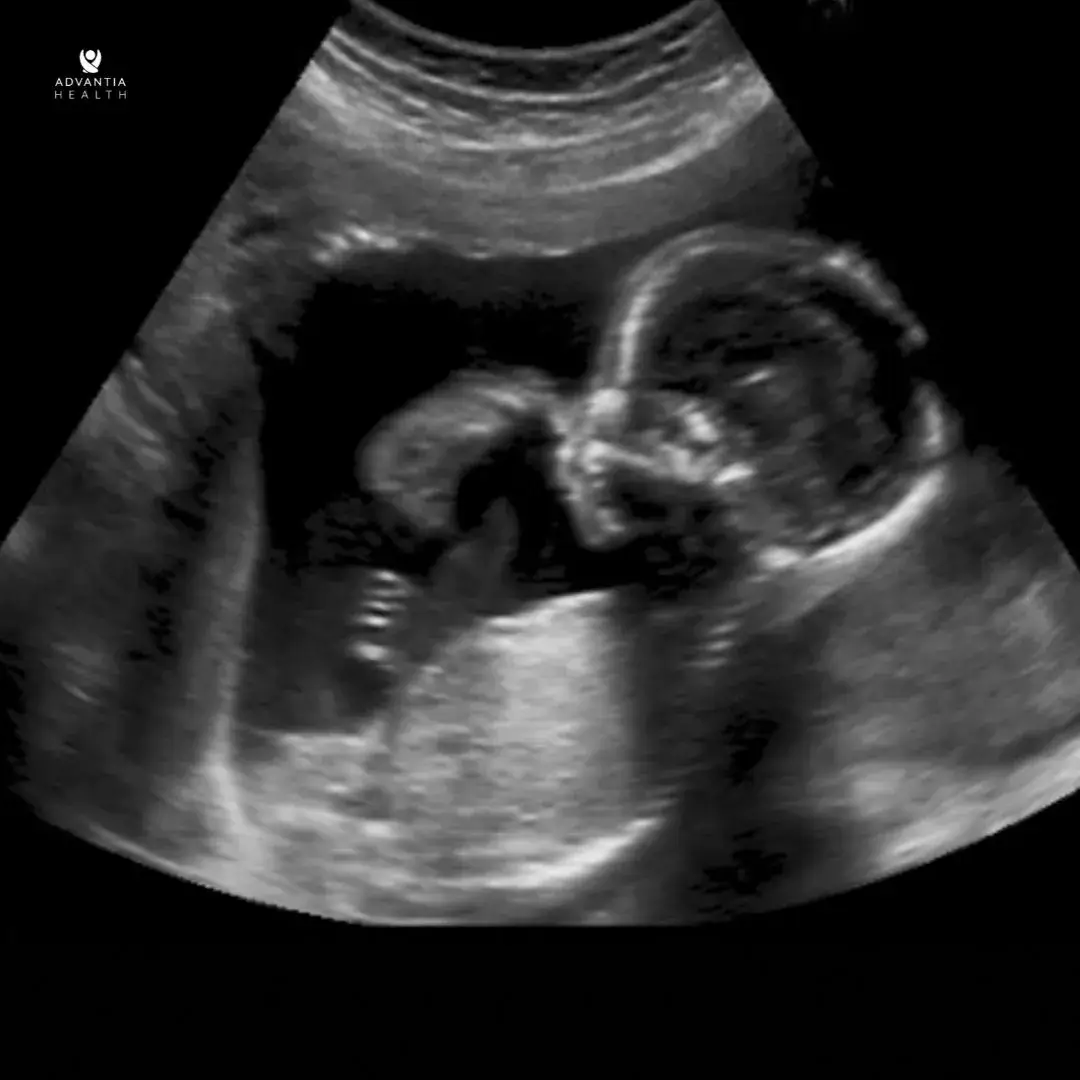

During the anatomy scan, a skilled sonographer will utilize ultrasound technology to capture detailed images of the fetus. This process involves examining various aspects, such as the baby’s head, brain, spine, heart, stomach, kidneys, bladder, and limbs. The scan will also check the fluid around the baby, placenta, and cervix position. This gives important information about how the pregnancy is going and the health of the mother and baby.

Parents eagerly anticipate this opportunity to check on their baby’s progress. Usually done around 18-20 weeks into the pregnancy, this ultrasound checks the baby’s organs, limbs, and growth.